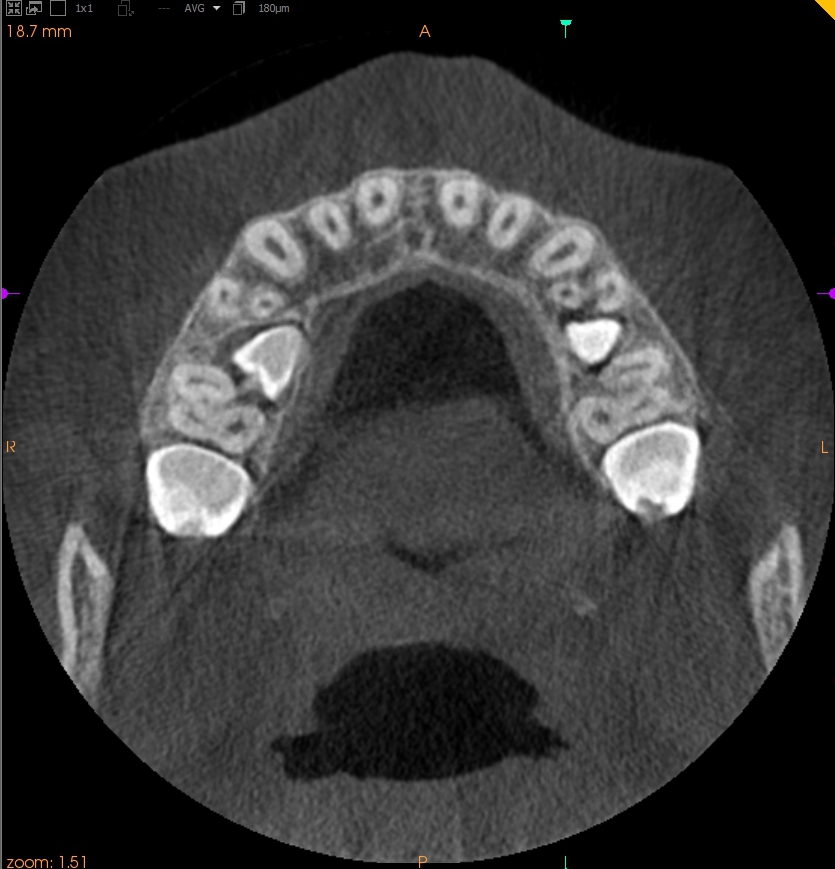

Resorpcja zęba to proces powstania ubytku twardych struktur zęba wywołanego przez osteoklasty bez kontaktu ze środowiskiem jamy ustnej, między innymi na skutek ucisku wywieranego przez ząb zatrzymany. Dla lekarza ortodonty jest istotne ustalenie, czy zęby zatrzymane lub twory nadliczbowe powodują resorpcję zębów stojących w łuku w celu wczesnej eliminacji przyczyny resorpcji. Celem pracy jest przedstawienie opisu przypadku zastosowania tomografii stożkowej w diagnostyce nieprawidłowo położonych zawiązków zębów przedtrzonowych drugich górnych. Stwierdzono, że tomografia stożkowa jest skuteczną metodą oceny wczesnej resorpcji zewnętrznej korzeni zębów.

Tooth resorption is the process of appearing of a defect of hard tissues of teeth caused by osteoclasts not having contact with oral cavity environment, eg. due to mechanical pressure exerted by an impacted tooth. It is essential for an orthodontist whether impacted teeth or supplementary teeth cause resorption of erupted teeth in order to early eliminate the causative factor of the resorption. The aim of the paper is to describe a case report of cone-beam computed tomography (CBCT) in diagnostics of incorrectly located germs of upper second premolars. It was found that CBCT was an efficient method of imaging of early external root resorption.